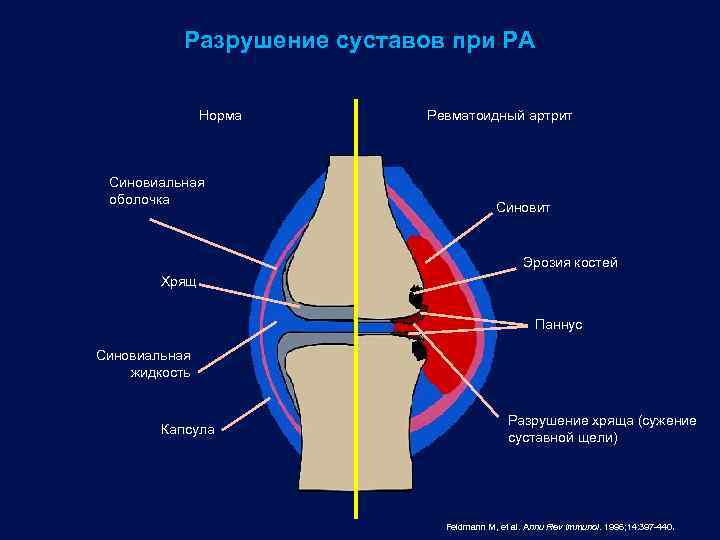

Разрушение суставов при РА Норма Синовиальная оболочка Ревматоидный артрит Синовит Эрозия костей Хрящ Паннус Синовиальная жидкость Капсула Разрушение хряща (сужение суставной щели) Feldmann M, et al. Annu Rev Immunol. 1996; 14: 397 -440.

Разрушение суставов при РА Норма Синовиальная оболочка Ревматоидный артрит Синовит Эрозия костей Хрящ Паннус Синовиальная жидкость Капсула Разрушение хряща (сужение суставной щели) Feldmann M, et al. Annu Rev Immunol. 1996; 14: 397 -440.